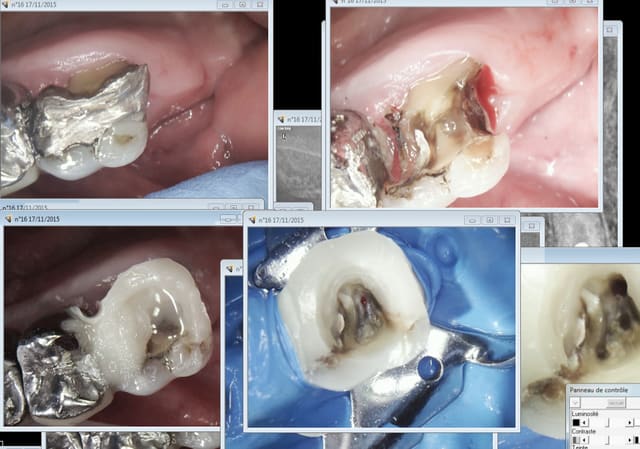

17/11/2015 à 13h23

Pour en revenir au sujet : peak universal bond sans etching et luxa core ca prend 2 mn. et je vais en chier pour la virer. -))))

Capture d e cran 2015 11 17 12.19 - Eugenol

Comment fais-tu pour remonter aussi bien tes parois et sans être gêné par la gencive ?

Pour faire un truc aussi net malgré la gencive là, là et là.

Rien du tout j'ai viré l'amalgame sans toucher la gencive . -))))